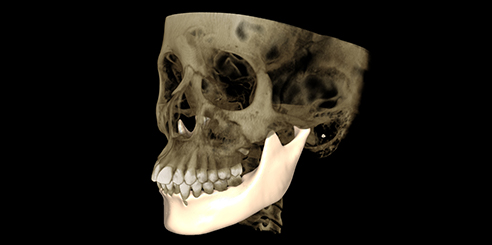

CT / CEPH / PAN Dental CBCT Functions

The LargeV CBCT supports CT, CEPH, and panoramic imaging in one compact system.

It delivers sharp, high-contrast images that reveal every dental structure with exceptional clarity.

High-Resolution Dental CBCT Imaging

The system achieves image resolutions up to 2.0 lp/mm with a voxel size range of 0.05 – 0.25 mm.

Its 0.5 mm small focus tube guarantees smooth, stable, and reliable scans.

Furthermore, the high-definition image output ensures accurate diagnosis and confident treatment planning.